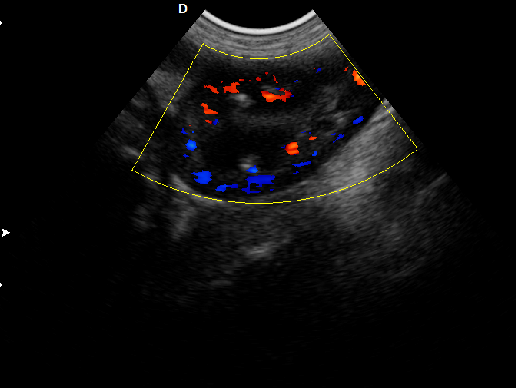

頸動(dòng)脈血流:

頸動(dòng)脈彩超是診斷、評(píng)估頸動(dòng)脈壁病變的有效手段之一,在動(dòng)脈粥樣硬化的流行病學(xué)調(diào)查和對(duì)動(dòng)脈粥樣硬化預(yù)防、治療試驗(yàn)的有效性評(píng)價(jià)中起著關(guān)鍵作用。

頸動(dòng)脈彩超不僅能清晰顯示血管內(nèi)中膜是否增厚、有無(wú)斑塊形成、斑塊形成的部位、大小、是否有血管狹窄及狹窄程度、有無(wú)閉塞等詳細(xì)情況, 并能進(jìn)行準(zhǔn)確的測(cè)量及定位,還能對(duì)檢測(cè)動(dòng)脈的血流動(dòng)力學(xué)結(jié)果進(jìn)行分析。